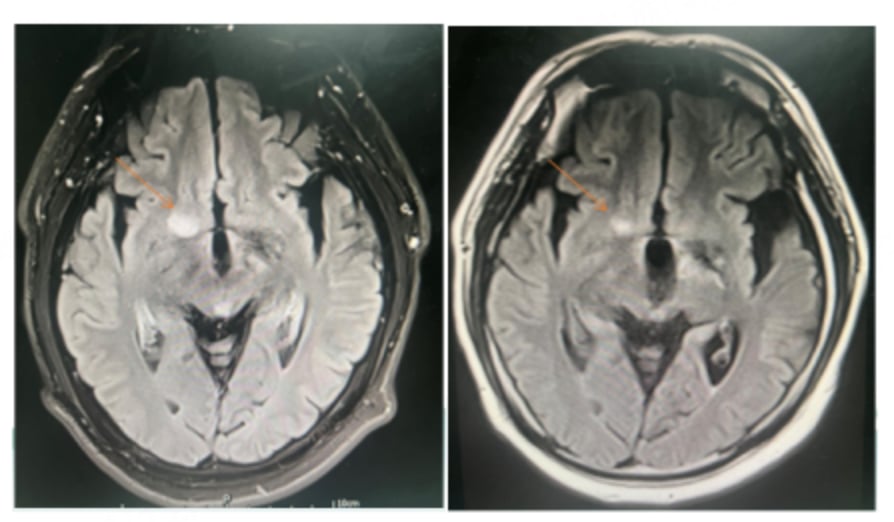

面对棘手的病情,医生同样采用了基于替尼泊苷的联合化疗方案。在第一个疗程后,患者出现了粒细胞缺乏伴发热的副作用,医生及时将后续化疗剂量减少了25%。经过调整后的3个疗程治疗,患者的症状显著改善,复查影像显示病灶缩小,同样达到了部分缓解(PR)。

这个病例说明,即使对于年龄较大且出现较严重不良反应的患者,通过适当调整剂量,替尼泊苷方案依然能够安全、有效地控制疾病。如果您对治疗方案或副作用管理有疑问,可以咨询MedFind的AI问诊服务。